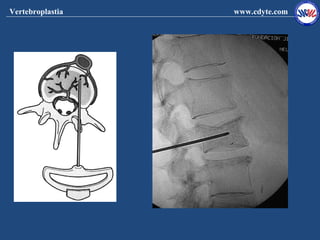

Técnica

1 Colocación del paciente y neuroleptoanestesia

2 Colocación de la aguja

3 Inyección del cemento

4 Comprobación clínico radiografica de la colocación

del cemento